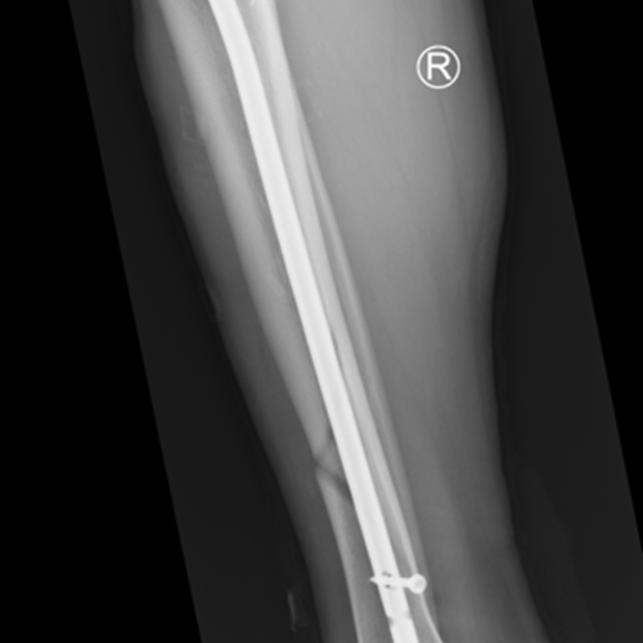

Zdjęcie 2.

Zdjęcia przedstawiają etapy gojenia (zrostu wtórnego), złamania kości piszczelowej zespolonej gwoździem śródszpikowym, od złamania do uzyskania zrostu.